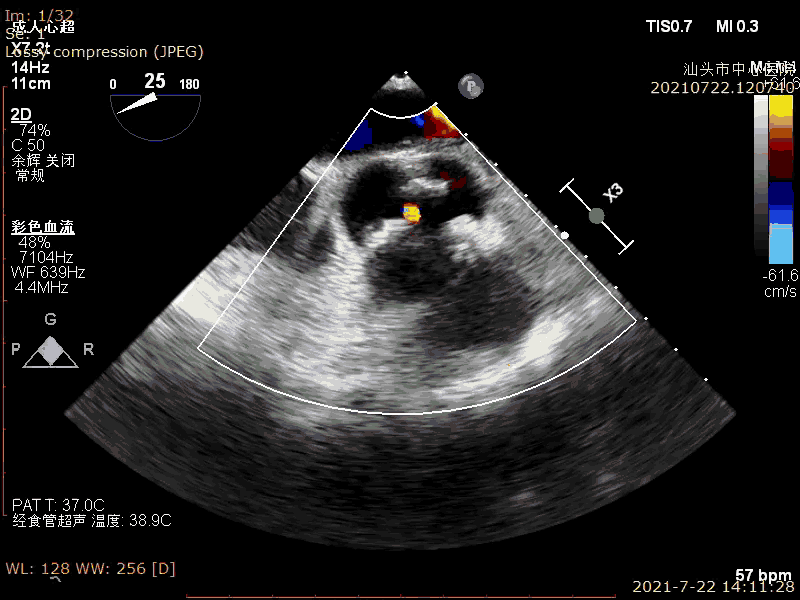

术前超声

超声示:

LVEF:70%

重度主动脉瓣狭窄并中度反流